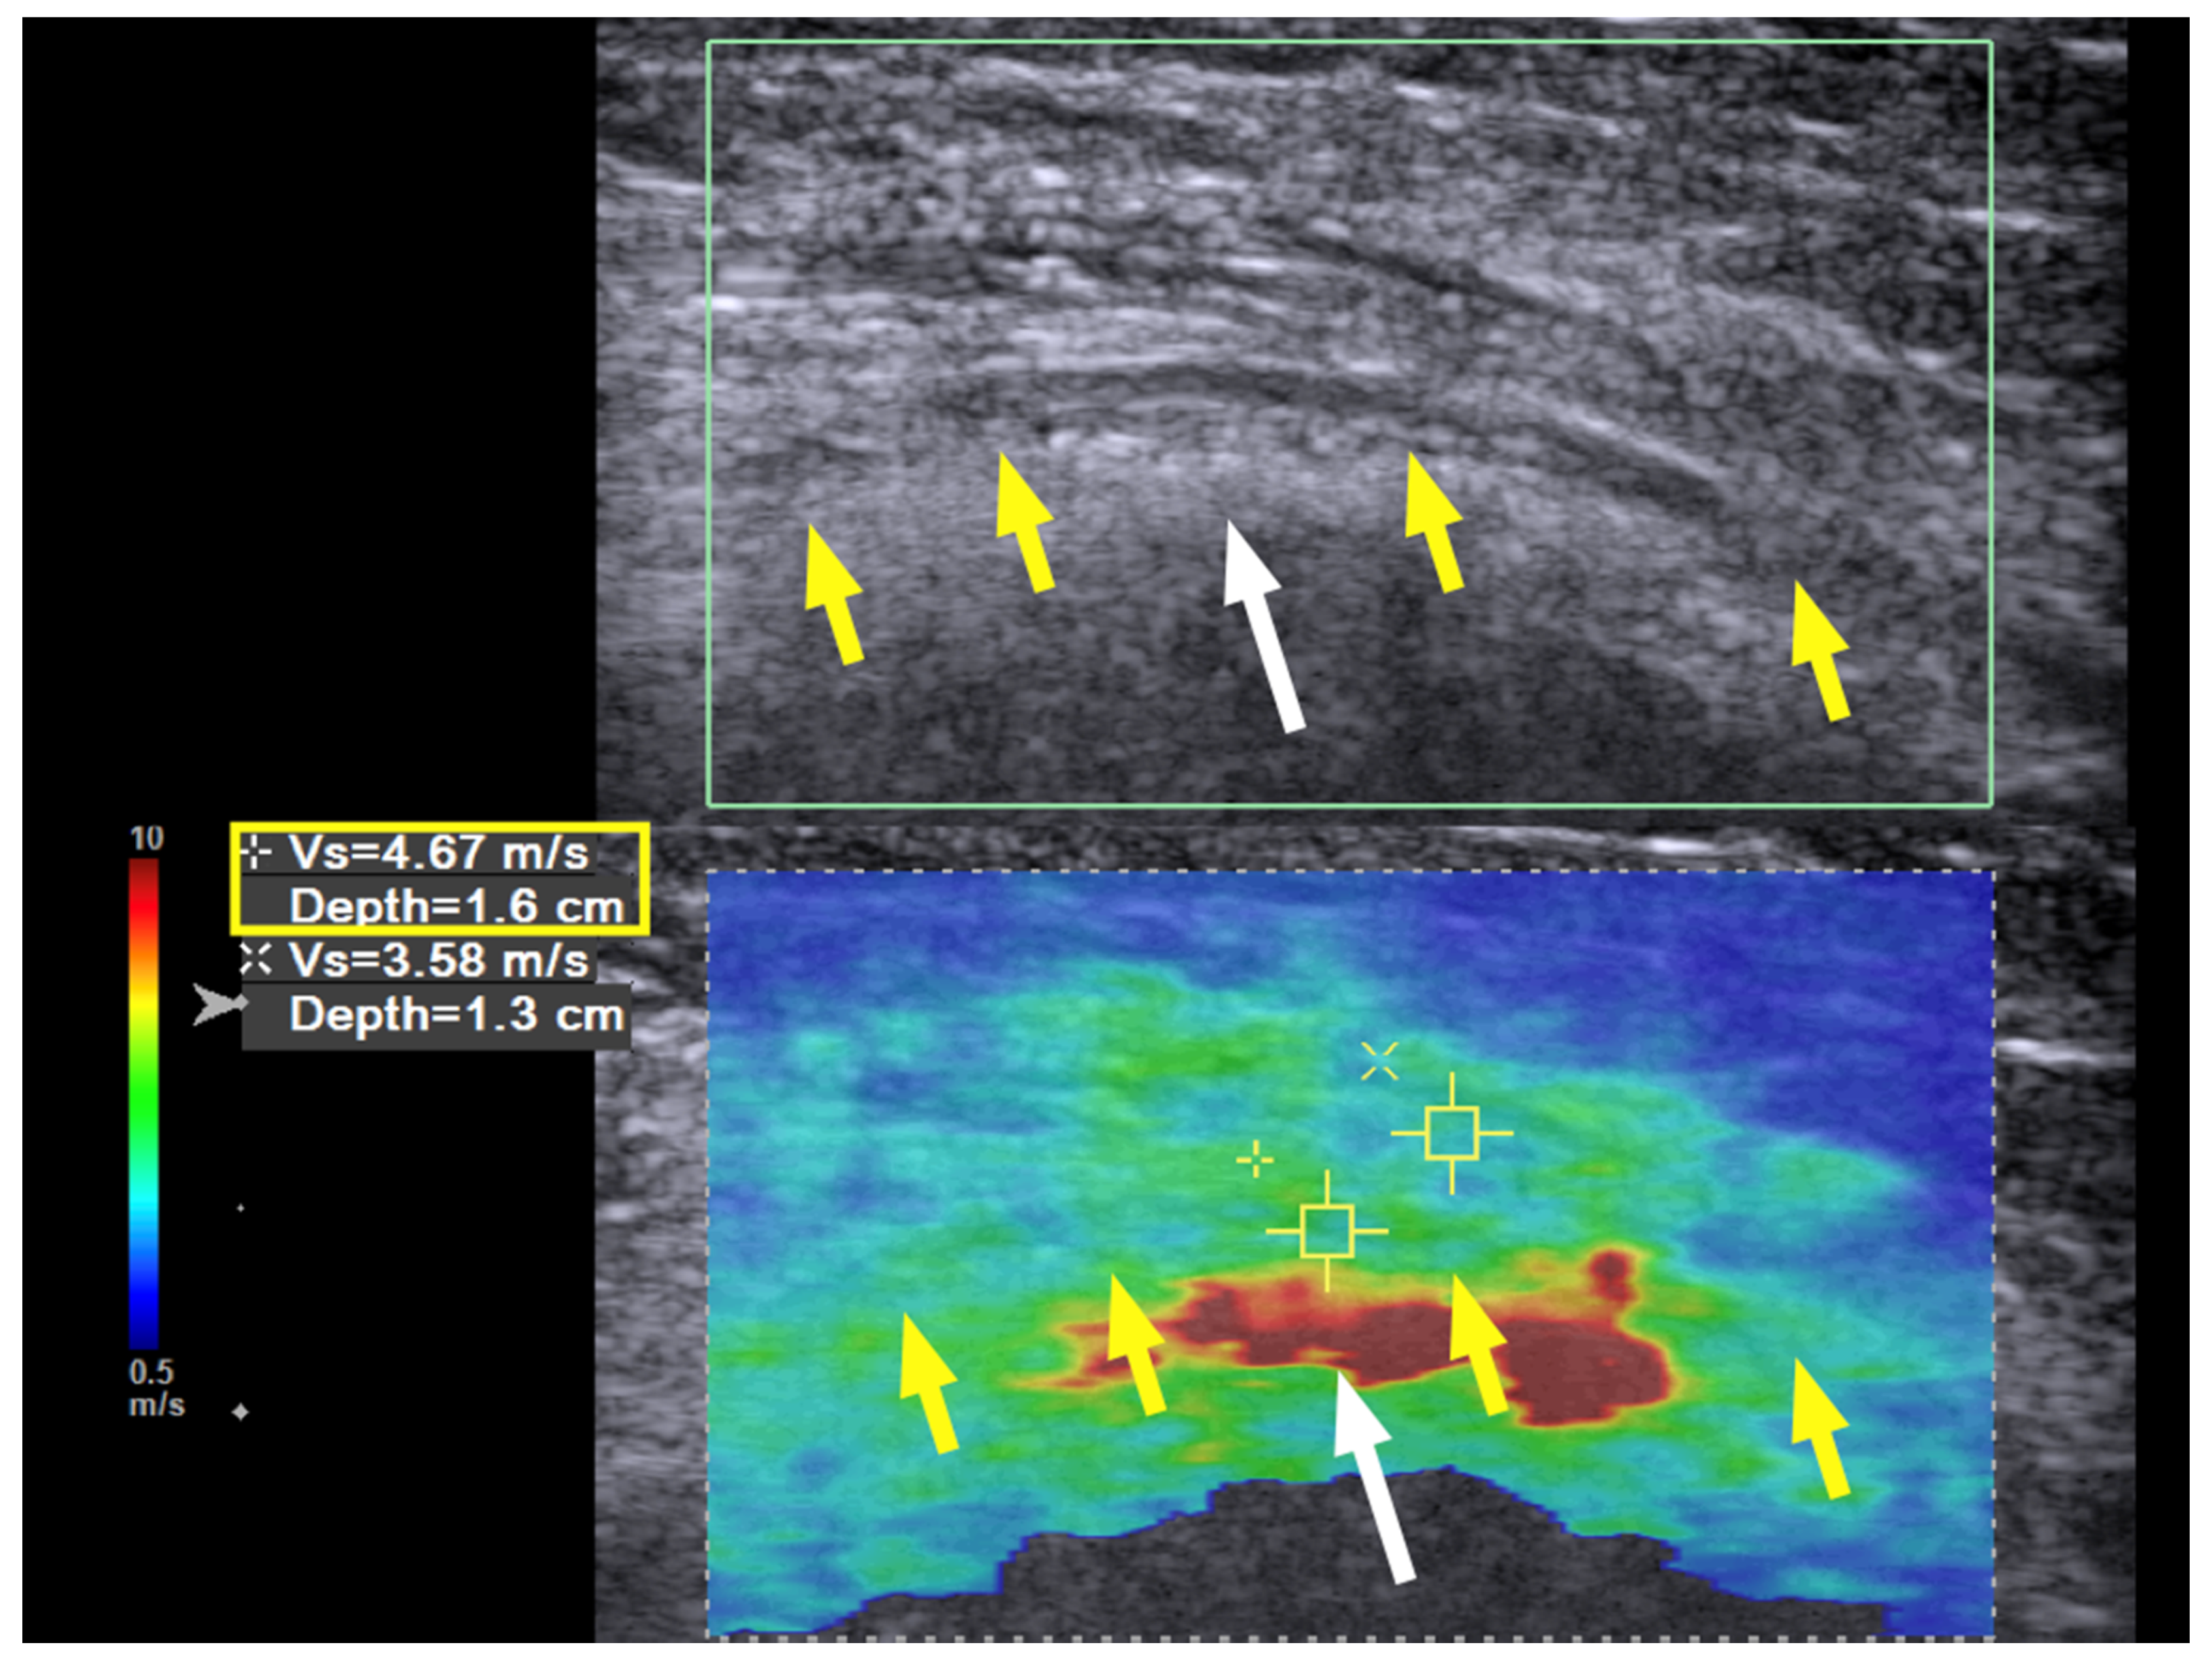

Three months later, the neuropathic pain was completely resolved, the muscle power of the ECRL and EDC had increased to 4+ (near normal), and the EIP had increased to 4; the neurodiagnostic study showed reinnervation over the EIP as well. The SWE revealed a further decrease in the hardness to 4.67 m/s at the previous entrapment site at the entrance to the spiral groove (Figure 4, yellow box). No further treatment was required, and the patient had regained full motor function with no numbness at the last follow-up 21 months after the hydrodissection.

Figure 4. Case 1: Shear wave velocity nine months after hydrodissection. Shear wave velocity (SWV) investigation of the radial nerve (long axis) over the spiral groove. Nine months after the first hydrodissection, the hardness of the nerve has returned to near normal, with a shear wave velocity of 4.67 m/s. Yellow arrow and box: radial nerve in longitudinal view; white arrow: bony cortex of humerus.